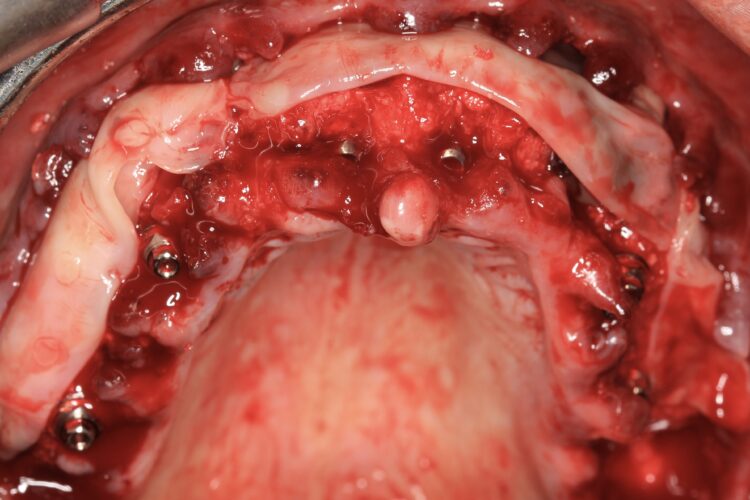

The implant beds were then prepared with the surgical guide in situ. Six CONELOG® Progressive-Line implants from BioHorizons Camlog were placed in accordance with the predetermined positions, depths and angulations. These implants were selected for this case because they feature an optimal thread design and tapered figure, promoting high primary stability – which is essential in full arch reconstruction cases.

The implants were placed through the guide for better accuracy and precision. A surgical primary stability of >35Ncm was achieved for each implant. Once the implants were placed, the surgical guide was removed, and the extraction of the remaining teeth was completed.

In preparation for the provisional prosthesis, straight multi-unit abutments were fitted onto the implants and torqued to 25Ncm, followed by titanium cylinders. For the anterior implants in the areas of the central incisors, the Comfour Straight bar abutments were used. The narrow prosthetic platform of these Comfour abutments (4.3mm) compared to the wider prosthetic platform of the standard multi-unit abutments is advantageous as it provides more space for soft tissue thickness and stability of the therapeutic outcome in the long-run.

A full thickness flap was reflected buccally up to the mucogingival junction followed by a split thickness flap with periosteal relieving incisions. Bone grafting materials were inserted into the sockets following socket preservation techniques. We used Mineralized Bone Allograft (MinerOss® by BioHorizons) mixed with autogenous bone particles collected during the drilling protocol, both inside the sockets and around the dental implants to fill the jumping gaps to the residual bone. Six 10ml tubes of blood were collected and L-PRF membranes were placed buccally to improve soft tissue healing and quality.

The finished and polished provisional restoration was screwed on the multiunit abutments at 15Ncm. The buccal flap was coronally advanced and closed with sling sutures using resorbable monofilament Glycolon 5/0 sutures.